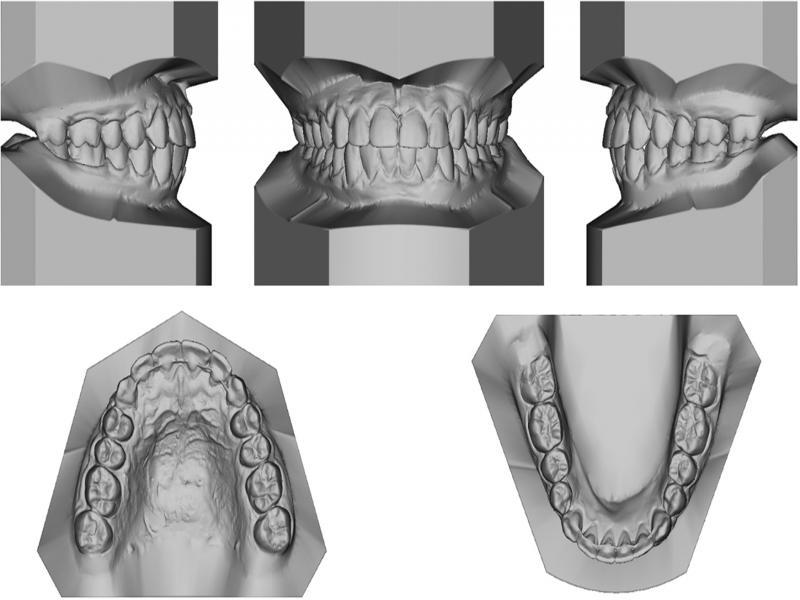

Figure 2.